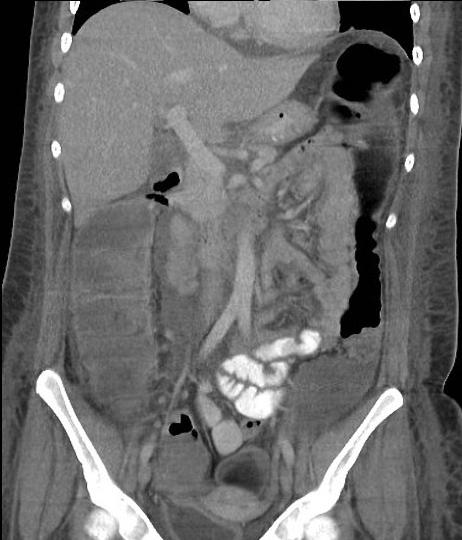

Toxic megacolon dans

maladie de Crohn . Image de distension du colon

transverse avec image de stenose inflamatoire et

epaissisement du colon sigmoigienne . Image

radiologique TDM en coupe coronale |

Meme cas en

coupe coronal a traver la colon transverse

. Maladie |